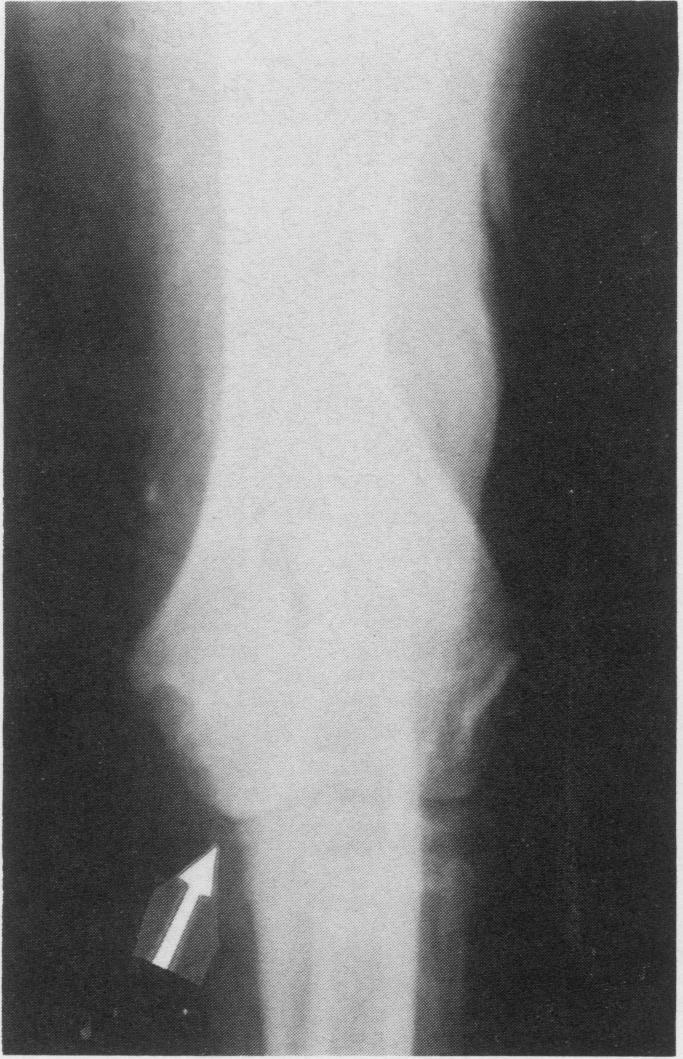

The presence of an ununited coronoid process, an ununited anconeal process and an ectopic proximolateral radial ossification center are described in a single elbow joint of a ten month old unspayed Great Dane. This animal and a nine month old spayed Saint Bernard, also with an ununited coronoid process, both had marked degenerative osteoarthritis associated with the instabilities.Chronic lameness and significant palpable elbow joint enlargement(s) were apparent in both dogs. Radiography was used to identify the lesions and surgical treatment produced satisfactory remission of signs.

在一只10个月大未绝育的大丹犬的单个肘关节中,发现了冠状突未愈合、肘突未愈合以及近端桡骨异位骨化中心。这只动物和一只9个月大已绝育的圣伯纳犬,同样有冠状突未愈合的情况,二者均有与关节不稳定相关的明显退行性骨关节炎。两只狗都有慢性跛行且肘关节明显肿大。通过放射摄影来识别病变,手术治疗使症状得到了令人满意的缓解。